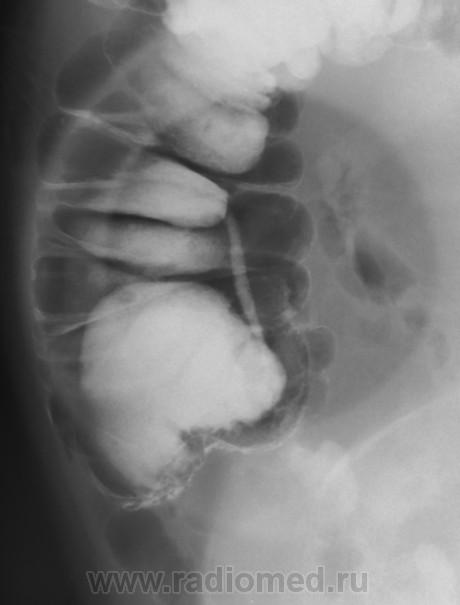

Такое ощущение, что слепая до конца не заполнилась. По-моему, я выставлял этот случай на сайте, но уж очень похоже. Никакими усилиями не возможно было заполнить слепую, хотя подозрения были. Только после т.н. опорожнения барий заполнил раковый канал.

Вполне может быть рак слепой кишки.

Согласен: купол слепой кишки выглядит ненормально, но возможно в результате операции. Вообще-то для большей ясности полагается контрастировать терминальный отд. подвздошной кишки. А колоноскопия здесь помогает не всегда.

ИМХО: слепая заполнена т.к. чётко видно обмазнный контрастом купол слепой кишки. Жаль, что не представлены R- граммы всех отделов толстой кишки.Показана фиброколоноскопия. При её безуспешности- РКТ брюшной полости, как компромиссный вариант УЗИ брюшной полости, для исключения синдрома поражения полого органа.